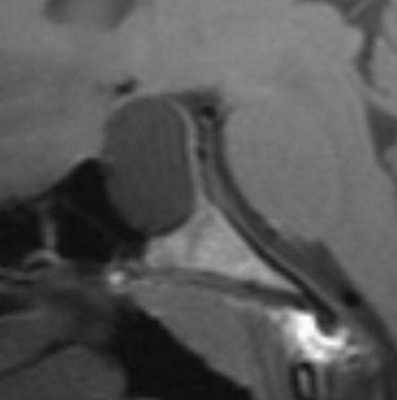

Киста кармана Ратке представляет собой редко встречающееся образование из остатков эмбриональной эктодермы (щель Ратке), расположенное между долями гипофиза. Выявляется в любом возрасте, но чаще в 50-60 лет. Клинические проявления связаны с масс-эффектом. При МРТ головного мозга выявляется небольшая (3-5мм) киста с четким контуром, без отека вокруг, однородная по структуре. Сигнал на МРТ головного мозга зависит от содержимого. При серозном содержимом сигнал типично жидкостный, при мукоидном киста светлая на Т1-взвешенных МРТ головного мозга. В 70-80% случаев внутри кисты выявляется неконирастирующийся узелок («пятно») - признак патогномоничный для кисты кармана Ратке. В редких случаях киста достигает больших размеров и даже выходит за пределы седла. Стенка кисты иногда усиливается при МРТ головного мозга с контрастированием. Дифференциальная диагностика при МРТ головного мозга должна проводиться с арахноидадьной и эпидермоидной кистами, тератомой, кистозной аденомой гипофиза и краниофарингиомой. Иногда при МРТ головного мозга киста кармана Ратке напоминает “пустое” турецкое седло. При маленьких размерах кисты ее на до дифференцировать на МРТ с микроаденомой гипофиза.

МРТ головного мозга. Т1-взвешенная сагиттальная МРТ. Киста кармана Ратке.